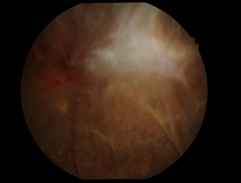

先日ハードレンズを処方した方の写真です。